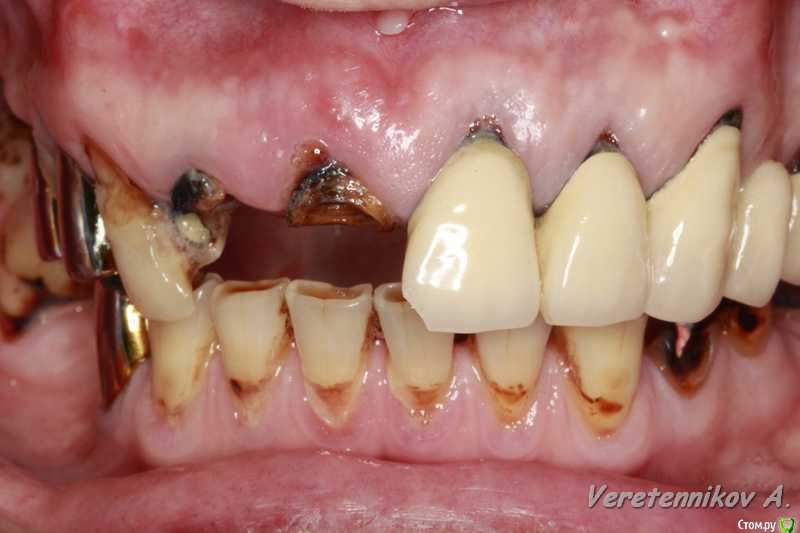

an_ver Опубликовано 26 марта, 2015 Поделиться Опубликовано 26 марта, 2015 (изменено) 11,12..11 трещина корня,вест.часть,12 рыхло все..сгнило.Убрал,кюретаж,11 вест. стенки нет на 2/3.Установил 11-4,2*13;12-3,75*13 мм..все Альфа.Мп3,мембрана эволюшн.11 заглушил,12-временный абатмент,коронка.Шил викрил 4,0. Фсе...пинайте Изменено 26 марта, 2015 пользователем an_ver 7 Ссылка на комментарий

Фарид Расулыч Опубликовано 26 марта, 2015 Поделиться Опубликовано 26 марта, 2015 Пациент с "шикарным" ртом))))) Все хочу так же попробовать времянки завремянить, но постоянно забываю снять слепок до удаления... лошпэ я.. Ссылка на комментарий

M@estro Опубликовано 26 марта, 2015 Поделиться Опубликовано 26 марта, 2015 Андрей, все вроде ок , смущает два вопроса навскидку. 1) непосредственная нагрузка консолью . Я бы так не рисковал .2) этап планирования. В таких кейсах я предпочитаю все демонтировать - и оценить состояние зубов, и уже после этого планировать удаления / имплантацию. Объясни, почему так поступил? 5 Ссылка на комментарий

zubovnet Опубликовано 28 марта, 2015 Поделиться Опубликовано 28 марта, 2015 (изменено) Понравилось. Смело. Но меня тоже консоль смущает...... Я бы не рискнул ТАК нагружать.вообще консоль на имплантанте это разве норм? Каппу бы ему сделали прозрачную, а там где удалились зубы- пластмасски беленькой. И раскручивайте на снятие соседей- там, видать , тоже все печально Изменено 28 марта, 2015 пользователем zubovnet 1 Ссылка на комментарий